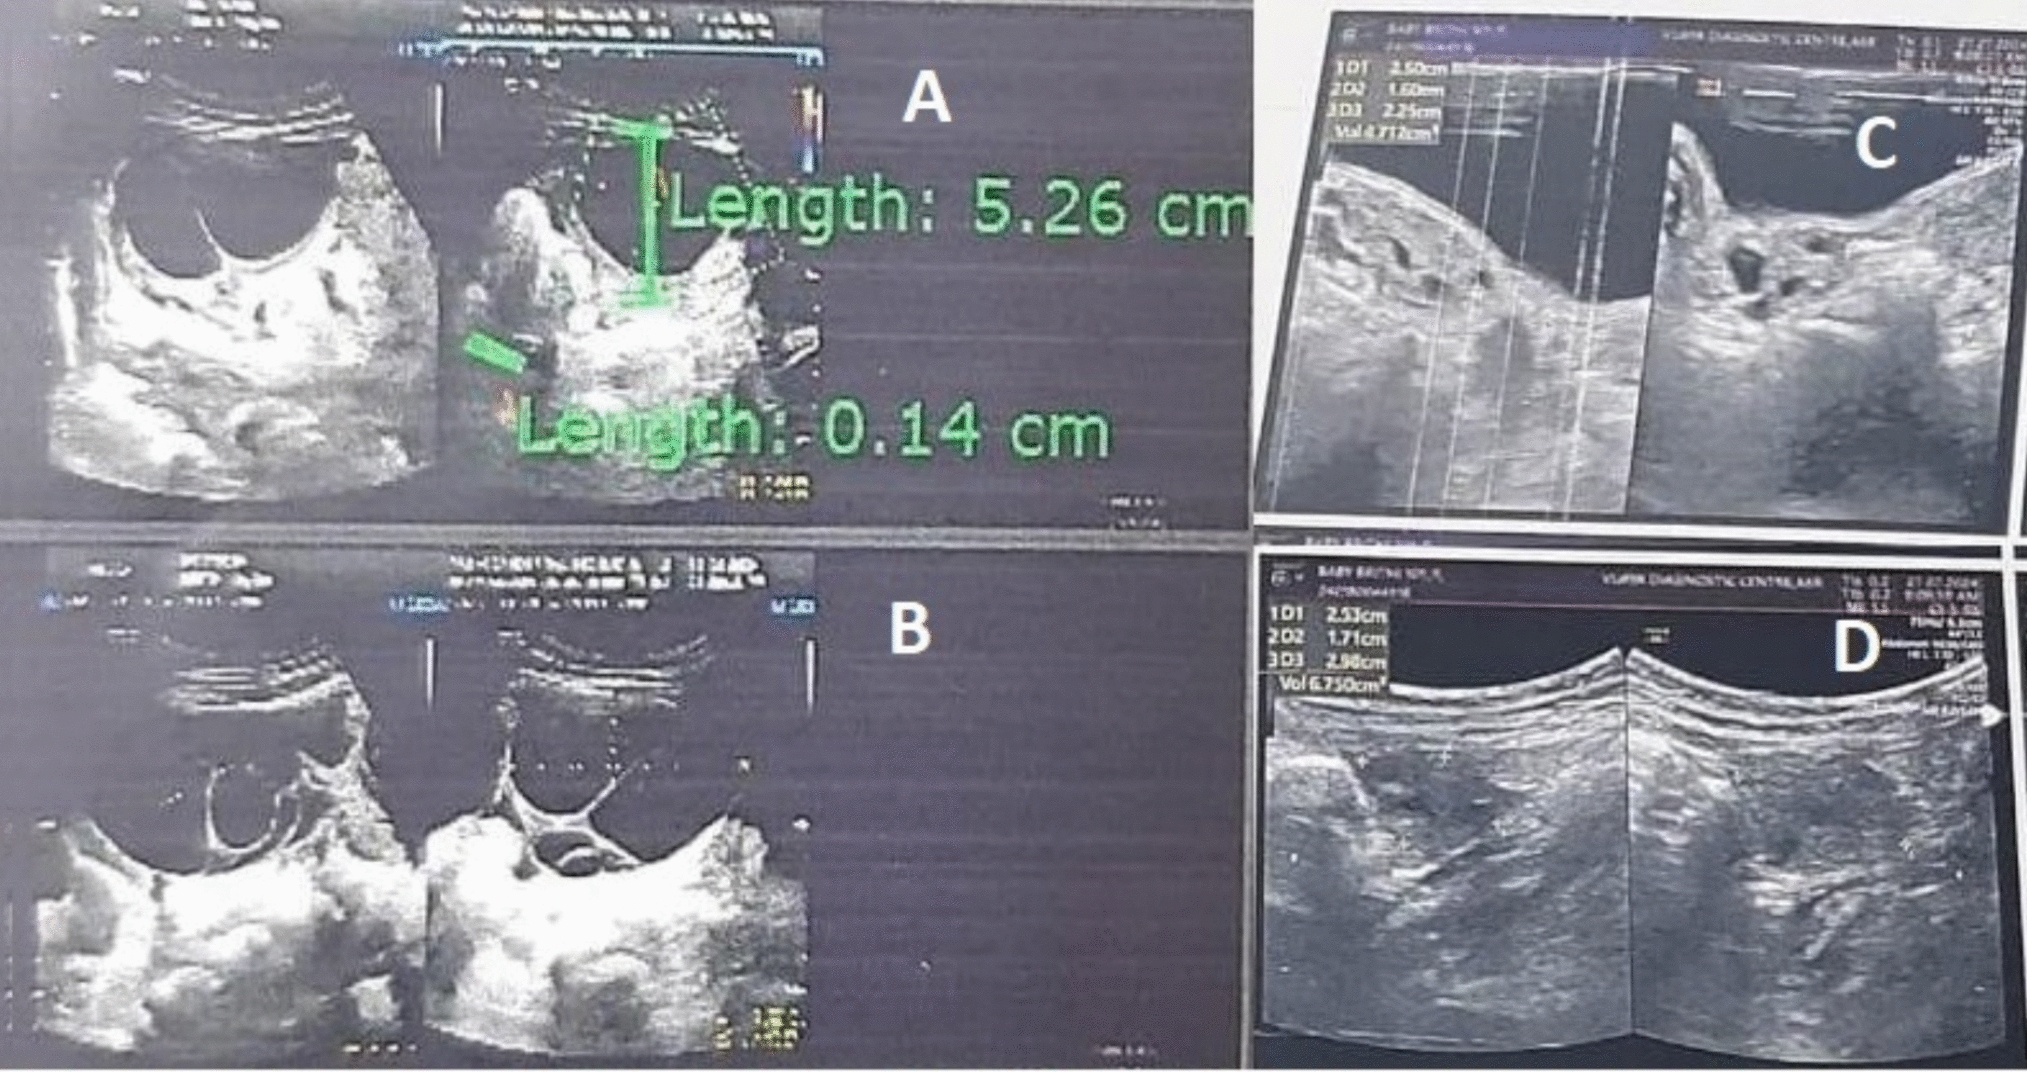

This was a retrospective observational cohort study of 154 patients with endometriosis who underwent laparoscopic or robotic endometriosis excision between April 2021 and September 2022 by a single surgeon in a multidisciplinary endometriosis centre. Clinical criteria such as age, demographics, menstrual history, previous endometriosis surgeries, size and location of endometriomas, along with clinical symptoms such as dysmenorrhea, dyschezia, infertility, dyspareunia, urinary frequency and rectal pain were documented. The #ENZIAN [2021] classification was used to assess the distribution of disease.

Mean age of the patients was 32.25 ± 6.107 years, and mean BMI was 23.9 ± 3.36 kg/m2. 47.2% had taken medical treatment for a period of 5.9 ± 11.7 months. Regarding parity, 75.4% were nulliparous, and 40.8% patients had infertility as co-existing complaint. According to #ENZIAN, the left ovarian involvement was observed in 67.4% and bilateral involvement noted in 46.1%. A (rectovaginal vagina and septum) was involved in 61% cases, B (uterosacral ligaments and pelvic wall) 63.58% on left and 60.33% on right and C (rectum and sigmoid colon) 33.1% cases.